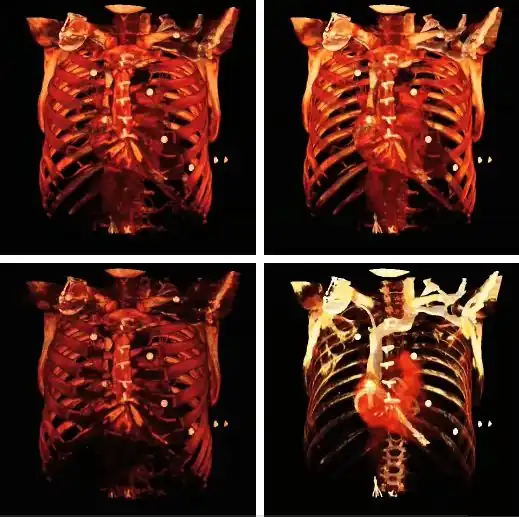

The influence on volume rendering of various shading settings is shown below:

The shading settings used for the above images are as follows:

| Image | Ambient Coefficient | Diffuse Coefficient | Specular Coefficient | Specular Power |

|---|---|---|---|---|

| Top Left | 0.15

|

0.9

0.3

15.0

| Top Middle | 0.75

| Top Right | 0.15

0.1

| Bottom Left | 0.15

1.2

| Bottom Middle | 0.15

1.0

| Bottom Right | 0.15

0.6